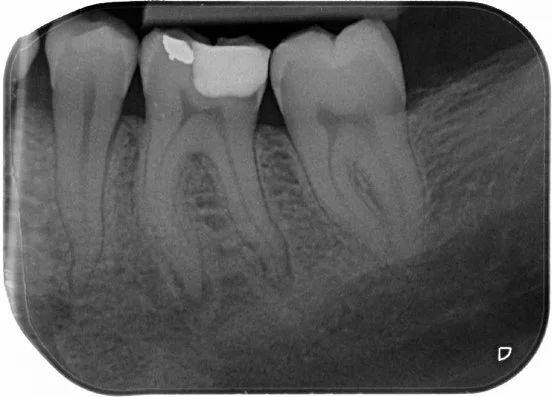

Pre-op PA of LL6 showing a deep DO restoration with secondary caries and apical radiolucencies.